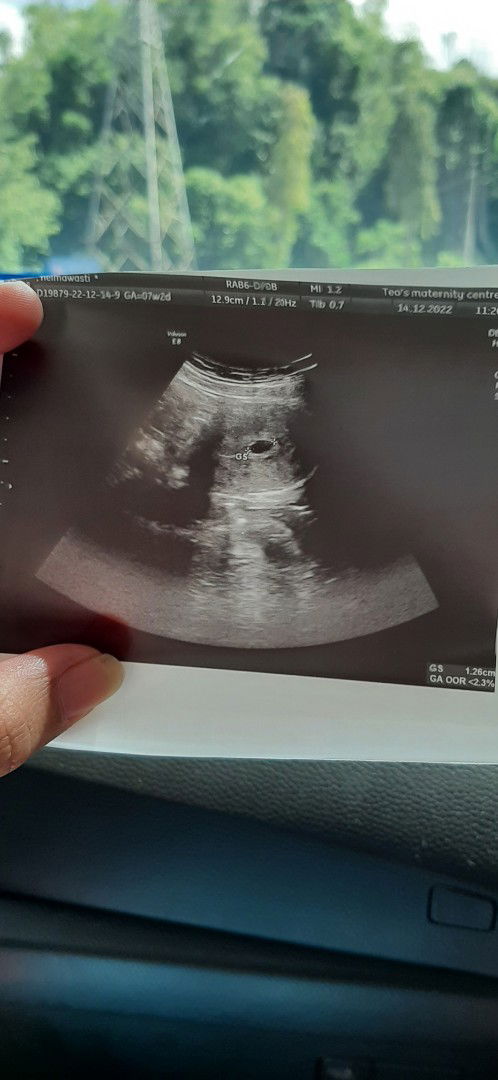

Pregnant 7weeks

Hallo mommies,nak tnya yg hitam tu baby ker atau kantung ??? Jgn kecam😁